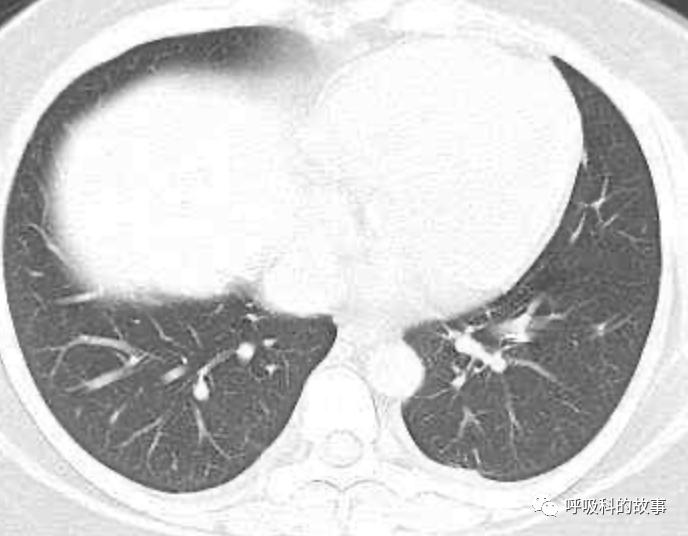

上面三张图分别是第一、二、三周的体温单

患者发热后行胸部CT检查(6月21日,住院第13天),可见两下肺有条片影,当时考虑是肺炎引起的发热。